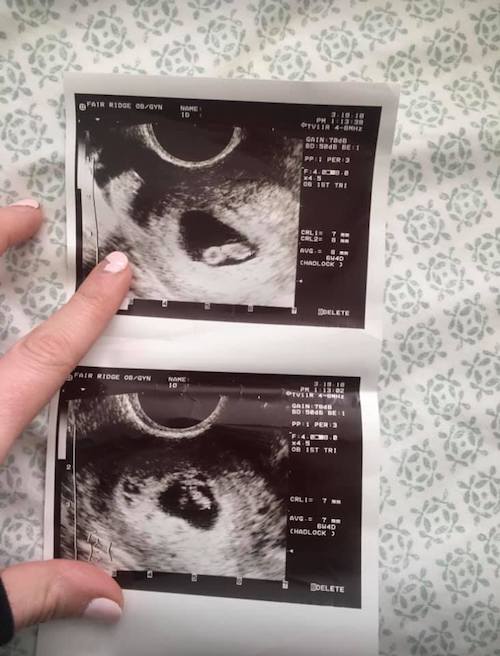

What Does an Ultrasound Look like at 6 Weeks Pregnant With Twins?

The earliest your doctor would likely order an ultrasound confirming twins would be 4 weeks pregnant. But unless you are going through fertility treatments, doing an ultrasound before 6 weeks isn’t very common, with the exception of complications. Women who are going through fertility treatments or have early complications may be able to have an early twin ultrasound at 4 or 5 weeks pregnant and find out they are pregnant with twins.

At four to five weeks after a pregnant woman’s last period the ultrasound commonly shows a small collection of fluid within the lining of the uterus that represents the early development of the gestational sac. At about five and a half weeks after a pregnant woman’s last period the ultrasound typically shows a gestational sac and within it we can see a 3-5 mm bubble-like structure, which is the yolk sac. At approximately six weeks after a pregnant woman’s last period, we can see a small fetal pole, one of the first stages of growth for an embryo, which develops alongside the yolk sac. UT Southwestern Medical Center